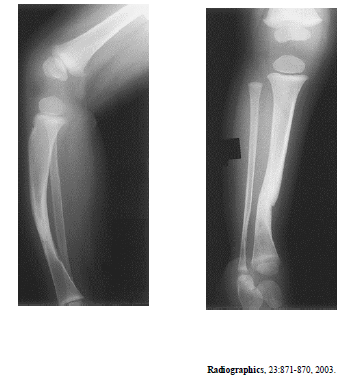

As radiografias acima são de um paciente do sexo feminino com um ano de idade. Com base nessas radiografias, é correto afirmar que

a porção identificada do fêmur tem aspecto normal.

as imagens revelam esclerose cortical no terço inferior da tíbia.

o raquitismo pode apresentar alterações semelhantes.

o principal diagnóstico é tibia vara (doença de Blount).

esse quadro radiológico pode ser justicado por neurofibromatose.

o paciente não possui a patela.